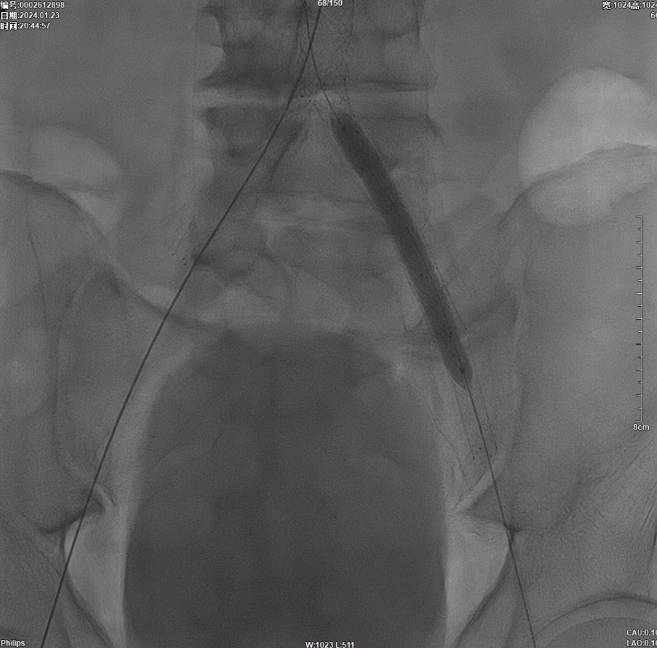

减容后造影显示仍存在重度残存狭窄,遂沿右侧股动脉置入VBX支架(直径11mm,长度59mm)。支架定位需满足近端完全覆盖腹主动脉病变段,远端距离双侧髂总动脉分叉至少1.5cm,以避免后扩张时大球囊对髂动脉造成损伤。

后扩张处理

首先使用14mm球囊进行初步扩张,鉴于腹主动脉直径约15mm,最终选用16mm球囊进行扩张。

当扩张压力达10 ATM时,患者出现轻微疼痛,遂停止扩张。扩张前需将左侧导丝撤出,扩张后重新置入并确认导丝位于支架内。